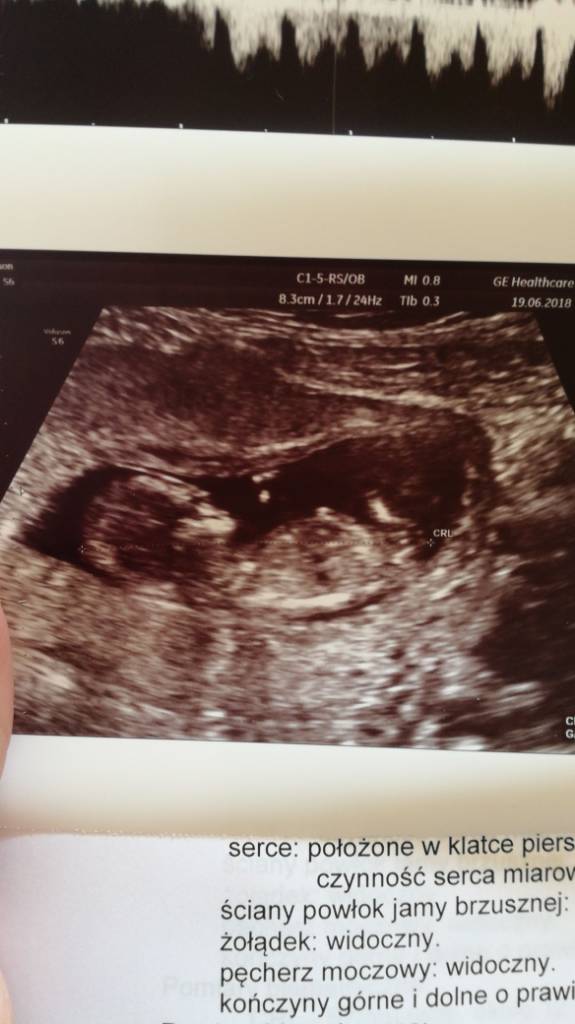

A to moje maleństwo z dzisiejszego USG genetycznego. Termin wg om mam na 5.01 a tu wyszło że na 30.12 [emoji51]

Zobacz załącznik 868818

Te z krwi to jest ten test pappa tak?Ale wyraźnie już widać, że to mały ludzik rośnie. I niech mi ktoś powie, że to nie jest cud [emoji173]️